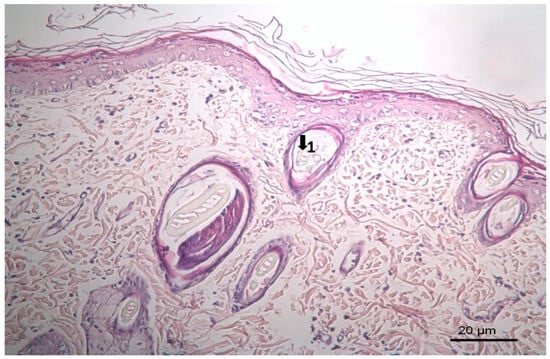

Figure 4. Histopathological view of wound healing in the control group (C). The skin sections show the hematoxylin and eosin stained epidermis and dermis. Arrows indicate events during wound healing; 1, neovascularization; 2, mononuclear cell; 3, fibroblast.

3.3. Histopathological Results

The results of histopathological observations are summarized in Table 12. Histopathological views of wound healing in the different groups are shown in Figure 4, Figure 5, Figure 6, Figure 7, and Figure 8 for C, P, M, CC, and LSC respectively. All results obtained from histopathologic observations were analyzed using the Kruskal–Wallis test for all histopathological parameters and Mann–Whitney U test for variations between two groups. Given all these results, the differences were significant in the wound healing phases of active and chronic inflammation, vascularization level, fibrosis, and fibroblastic activity. LSC was the best performing group in all favourable scores for the healing indicators.

Figure 5. Histopathological view of wound healing in the placebo group (P). The skin section shows the hematoxylin and eosin stained epidermis and dermis. Arrows indicate events during wound healing: 1, fibroblast; 2, neovascularization; 3, neutrophil; 4, congestion; 5, hair follicle.

Figure 6. Histopathological view of wound healing in the reference group (M). The skin section shows the hematoxylin and eosin stained epidermis and dermis. Arrows indicate events during wound healing; 1, hair follicle.

Figure 7. Histopathological view of wound healing in the complex group. The skin section shows the hematoxylin and eosin stained epidermis and dermis. Arrows indicate events during wound healing; 1, hair follicle; 2, collagen fiber.

Figure 8. Histopathological view of wound healing in the Levant storax group. The skin section shows the hematoxylin and eosin stained epidermis and dermis. Arrows indicate events during wound healing; 1, hair follicle; 2, collagen fiber.

The CC contained well-established actives such as aescin, Aloe vera, Allantoin, Calendula oil, and Hypericum perforatum extract. These herbal remedies are known for their fibroblast stimulation, anti-inflammatory, and anti-edematous effects [10,11,12,13,14,15,17,18], which translates to statistically significant improvements over C and PC groups in terms of wound contraction (Figure 3) and progressive changes in wound area measurements (Table 9 and Table 10). The results regarding full skin thickness regeneration are detailed in Table 11. The LSC group exhibited superior effects on skin thickness restoration, followed by the CC, which outperformed the P and C (control) groups, likely due to its fibroblast-stimulating constituents. Wound healing proceeds through hemostasis, inflammation, proliferation, and remodeling phases. Histopathological evaluations utilized cellular markers to delineate these stages: neutrophils and mononuclear cells as indicators of inflammation [56], while the recovery phase of wound healing is marked by fibrosis and hair follicle formation, decreased neovascularization, and disappearance of neutrophils and mononuclear cells [56,57,58]. In histopathological investigations of this study, neutrophils and mononuclear cells are used as indicators of the inflammation phase [56]. Histopathological views presented in Figure 4, Figure 5, Figure 6, Figure 7 and Figure 8 and a summary of results of the seen histopathological indicators (Table 12) showed minimal active inflammation, evidenced by low neutrophil presence across all groups. Chronic inflammation, defined by mononuclear cell infiltration [50,59,60], was absent in the LSC and CC groups but notable in the C and PC groups (Table 12), which underscored the anti-inflammatory properties of active ingredients. On the other hand, the proliferation phase is assessed by fibroblastic activity and neovascularization [56,57,58]. Fibroblast activity, critical for collagen synthesis and extracellular matrix production {5}, was also highest in the LSC group, aligning with its enhanced healing capacity. Neovascularization, essential for oxygenation and nutrient supply during new tissue formation [61,62] was significantly improved in LSC and CC groups compared with the other groups, supporting the multifaceted roles of the active contents in accelerating wound healing (Table 12). Fibrosis, defined as excessive collagen deposition leading to scar formation, was reduced in P and LSC groups, indicating less aberrant repair [60,63,64], and hair follicle neogenesis, which is an important parameter of advanced healing and regeneration and correlates with remodeling [60,64,65,66]. This was most pronounced in the LSC-treated wounds (Table 12, Figure 8). At the designated time point (day 9), wounds treated with LSC and CC had transitioned into the remodeling phase, while C- and PC-treated wounds remained in the proliferation phase. The M group was nearing remodeling (Figure 6). Collectively, these findings substantiate the superior wound healing efficacy of LSC and CC relative to others used as controls and comparisons.